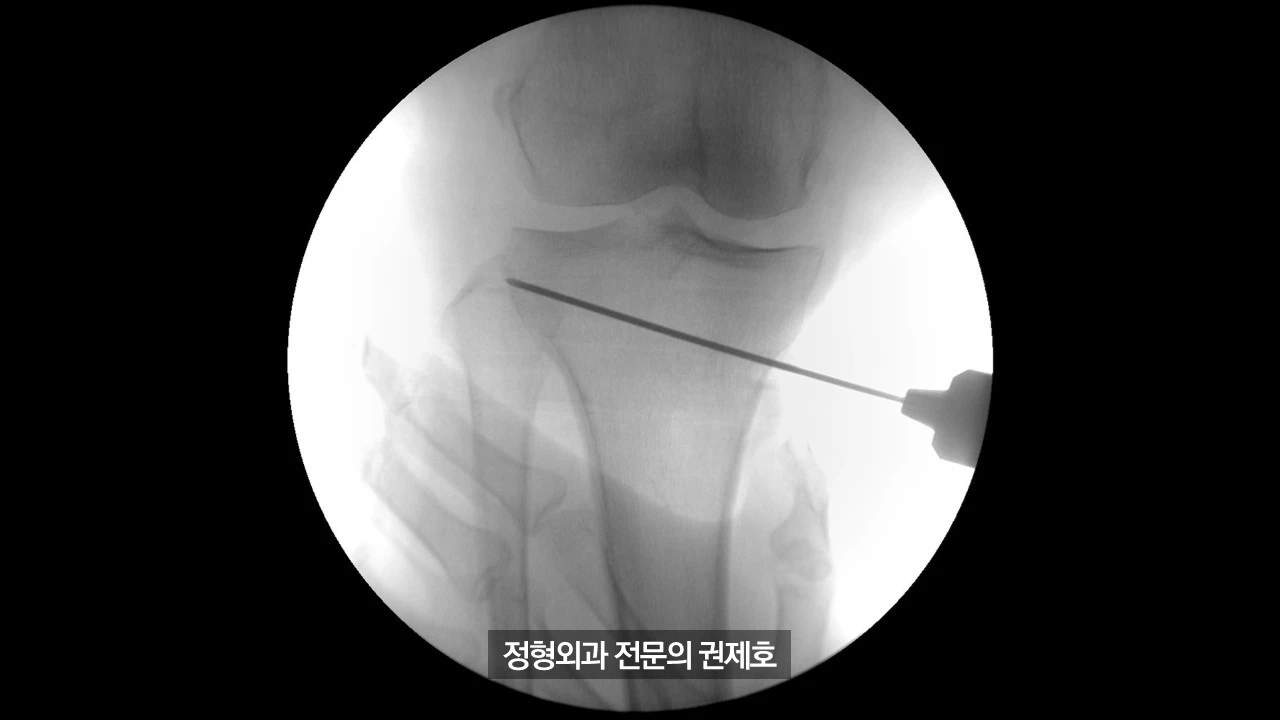

간이 엑스레이 기기를 통해 촬영한 사진이며 (좌측) 가이드 핀을 이용해서 절골할 길을 만드게 되고, (우측) 절골도를 이용하여 천천히 절골을 시행하게 됩니다.